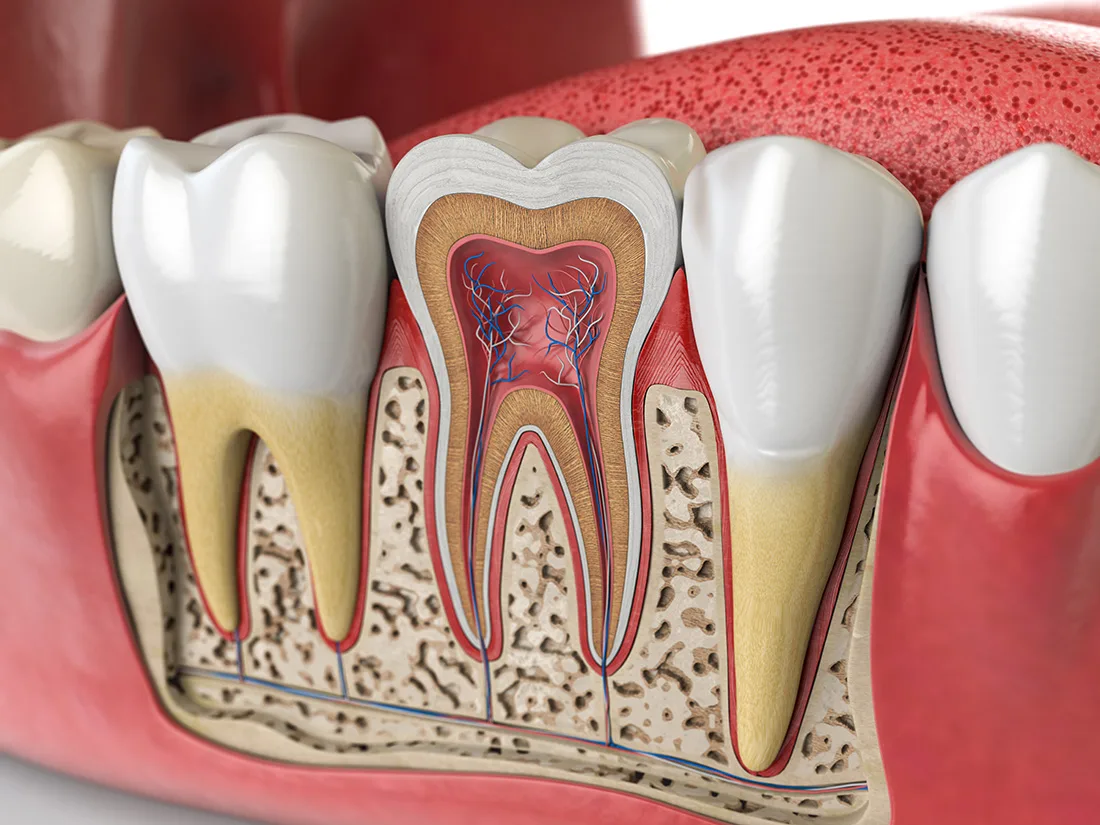

Removing Decay & Infected Pulp

Once you're fully numbed and comfortable, your dentist will begin the process of removing decayed or infected material. They'll start from the outermost layer of enamel and work their way towards the inner pulp. After removing the infected pulp, the canals will be thoroughly cleaned and flushed with a specialized disinfectant to eliminate any remaining infection.

Filling & Sealing

After cleaning and disinfecting your tooth, your dentist will fill the inner cavity with a rubbery substance called "gutta-percha". This inert material provides support to the tooth and replaces the extracted pulp. Following this, your dentist will determine whether to restore the tooth with a filling or a dental crown. This decision is based on the extent of decay and the amount of healthy enamel remaining on the tooth.

Root canal therapy is a specialized procedure designed to treat the innermost layer of the tooth—the dental pulp. When the pulp becomes inflamed or infected, it can lead to symptoms like lingering sensitivity to hot or cold, pain while chewing, or noticeable swelling. Root canal treatment helps relieve these symptoms, save your natural tooth, and prevent the need for extraction.